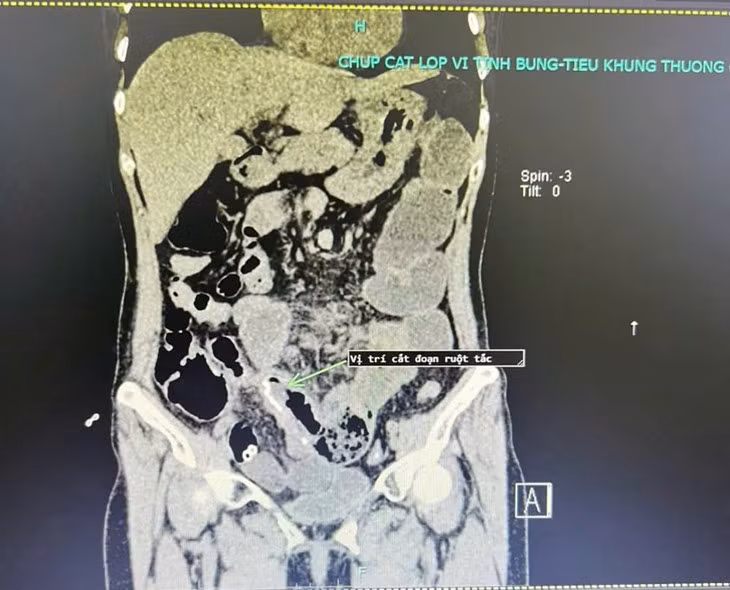

| Hình ảnh chụp cắt lớp vi tính cho thấy quai ruột tắc, giãn to khi vào viện. Ảnh BVCC |

Qua khai thác bệnh sử, người bệnh đã phẫu thuật cắt tử cung, cắt đoạn ruột non; dính ruột một lần năm 2022. Lần này, người bệnh thấy xuất hiện đau bụng kèm theo nôn gia đình đã cho nhập viện tại bệnh viện đa khoa tư nhân trên tỉnh Phú Thọ, được điều trị 10 ngày tuy nhiên không đỡ, người bệnh đã chủ động lên bệnh viện đa khoa tỉnh Phú Thọ khám.

Tại khoa Ngoại tổng hợp Bệnh viện đa khoa tỉnh Phú Thọ, người bệnh được chẩn đoán tắc ruột dính. Có chỉ định phẫu thuật gỡ dính, lập lại lưu thông ruột.

Trong mổ các BS nhận thấy các quai ruột non giãn to, dính gập góc gây tắc hoàn toàn đoạn hồi tràng gần góc hồi manh tràng. Các Bs đã tiến hành gỡ dính, cắt đoạn ruột tắc lập lại lưu thông ruột. Hiện tại, người bệnh đã ổn định và được ra viện.